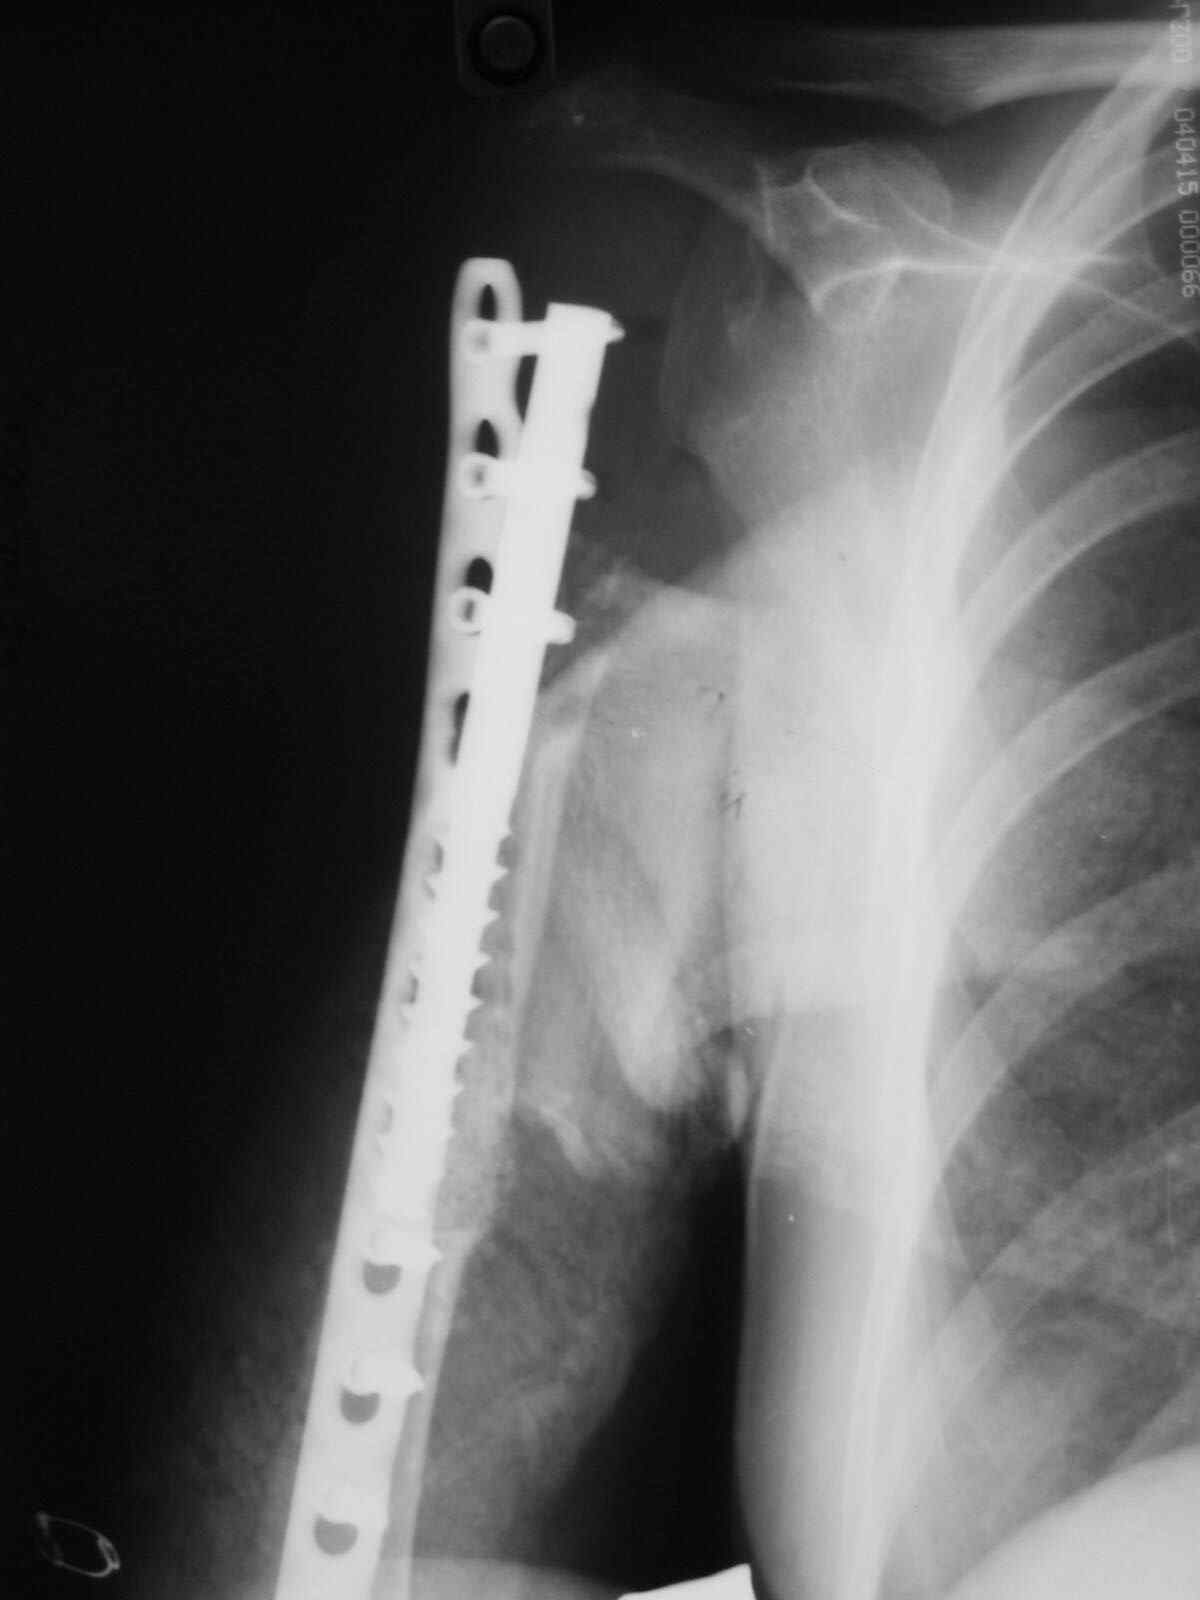

Больная 34 года операрована 14 лет назад по поводу литической формы ОБК головки плечвой кости

14 лет назад больной имлапнтирован протез плечевой кости выполненый по методике Воронцова на штифте-штопоре Сиваша,за 2 года до имлапнатации в онкологическом учереждении больной выполнена резекция проксимальоной части плечевой кости по поводу ОБК, ксенотрансплантации головки, и последующем его удалением на фоне гнойного процесса. У больной имелся втянутый обширный рубец и болтающееся плечо, афункциональная верхняя конечность, выраженный косметический дефект.П/опрационный период без осложнений, сохранялась выраженная контрактура в плечевом суставе, но стаилизация плеча и косметический эффект больную устраивал,даллее контакт с больной был утерян ( поменяла место жителсьтва. Через 14 лет полноценной жизни сельской жешщины ,больная нашла нас с клиникой выраженной нестабильности протеза. Категорически отказалась от замены протеза.

Выполнена операция- малоинвазивно проведена LCP пластина в образованный канал над головкой протеза, фиксирована к протезу и дистально к плечевой кости, на зоной резорбции трепонирована кость, удалена соединительно-тканная оболочка, полость заполнена chronOS. П/о период без осложнений, клиника нестабильность купирована.Прошло 2 года по телефону сообщила, что у нее все хорошо, продолжает жить счастливой жизнью сельской труженицы

Головка отлита из акрилоксида( то чем мы располагали в прошлом веке), он полность Р-прозрачен, по методике Воронцова рекомендовалось добавлять Р-контрастные добавки,например сульфат бария, учитывая, что он давал раковины в полимере, мы это не сделали.Кстати, довольно крепкий получился, затупили 2 сверла.

Функциональный результат нам известен в полеоперационном периоде

отведение 10 гр, сгибание 60 гр, разгибание 0, ротация 5гр, что соответсвовало функции до наступления нестабильности.

К сожаления, вся информация о нынешем состоянии больной получена по телефону - болей нет, объм движения не уменьшился, полная нагрузка на конечность, из наших рекомендаций по ограничениям соблюдает только одно- не выкручивает белье.